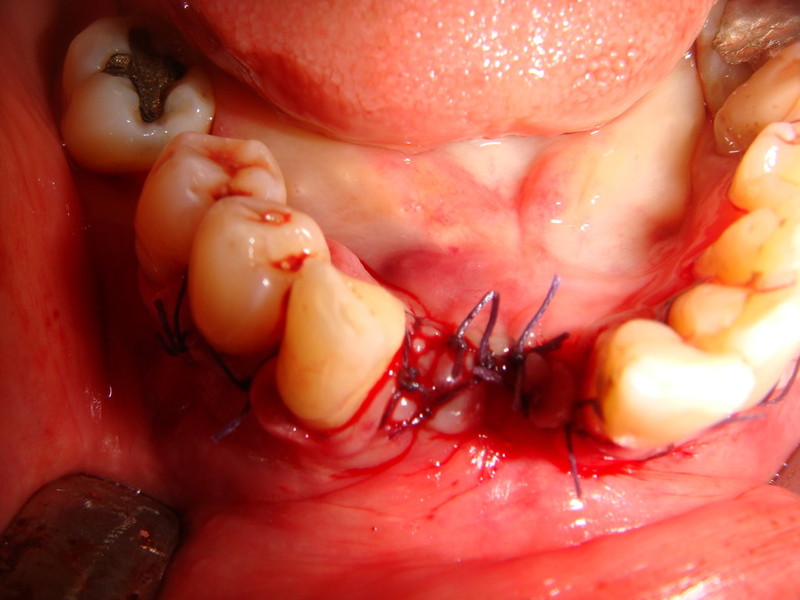

Rigenerazione difetto parodontale di un canino inferiore con materiale eterologo